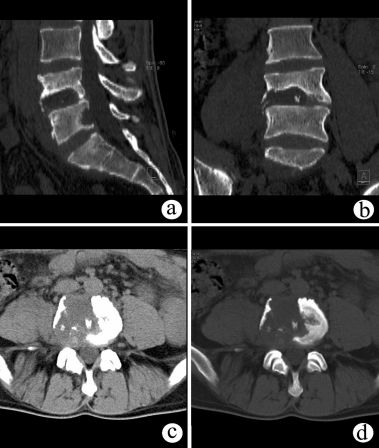

1、X线:部位、类型、程度;(正侧位、双斜位、动力位、颈椎张口位等)

2、CT:可显示椎体的骨折情况,可显示有无碎骨片突出于椎管内,计算椎管前后径损失了多少,不能显示脊髓受损情况。(平扫、薄扫、三维、表面重建等)

(2)爆裂骨折

椎体压缩骨折的一种特殊形式,椎体呈粉碎骨折,骨折块向四周移位,向后移位可压迫脊髓、神经,椎体前后径和横径均增加,两侧椎弓根距离加宽,椎体高度减小。